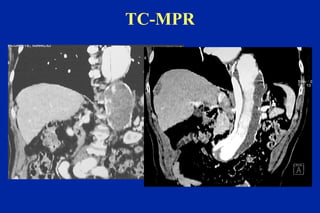

Este documento resume los principales tipos y técnicas de angiografía. Describe brevemente la angiografía, arteriografía, flebografía y linfografía, así como las técnicas de contraste y materiales utilizados. También explica los principales accesos vasculares, la técnica de Seldinger, la angiografía por sustracción digital y algunas técnicas endovasculares comunes.